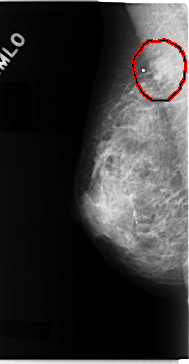

C_0077_1.RIGHT_MLO

RIGHT_MLO LINES 4728 PIXELS_PER_LINE 2456 BITS_PER_PIXEL 12 RESOLUTION 50 OVERLAY

FILE: C_0077_1.RIGHT_MLO.OVERLAY

TOTAL_ABNORMALITIES 1

ABNORMALITY 1

LESION_TYPE MASS SHAPE IRREGULAR MARGINS ILL_DEFINED

ASSESSMENT 4

SUBTLETY 3

PATHOLOGY MALIGNANT

TOTAL_OUTLINES 1

BOUNDARY